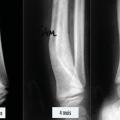

• l’embrochage centromédullaire élastique stable (ECMES) est une méthode couramment utilisée en traumatologie infantile. Elle consiste à mettre des broches cintrées et béquillées dans le canal médullaire et obtenir ainsi une stabilité élastique du foyer (fig. 10). Toute force appliquée sur l’os provoque un déplacement avec retour élastique à l’état d’équilibre qui est l’état anatomique ;12